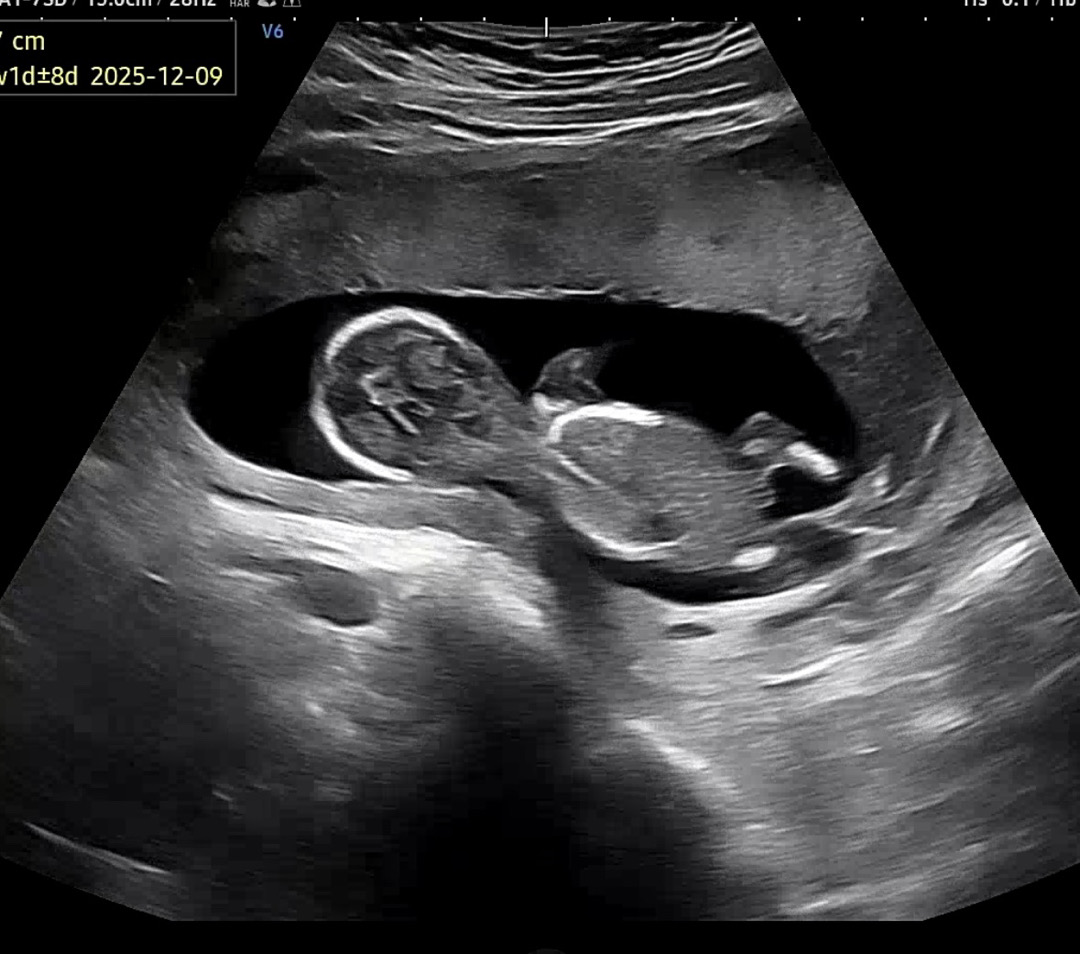

14주 성별 함 봐주세요ㅠㅠ

뒷모습에서 보이는 다리 사이에 저거 🌶️일까여…?

삼각점이 안 보여서 애매하긴 하지만 14주면 아들일 것 같네요!